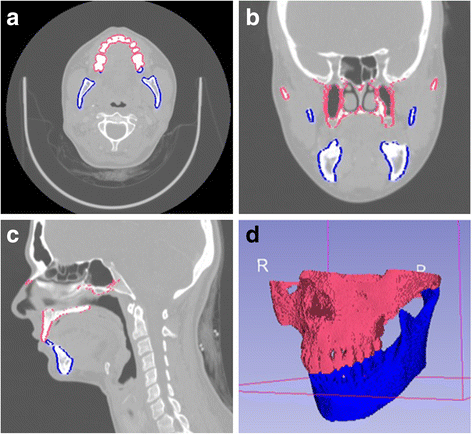

a) Axial, b) coronal and c) sagittal CT images obtained from 3D Slicer depicting the maxillary and mandibular anatomy with d) the corresponding 3D reconstruction